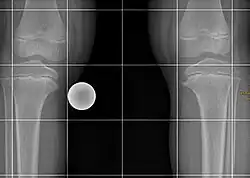

Die Blount-Krankheit, auch Blount-Syndrom oder Erlacher-Blount-Syndrom ist die kindliche Form der Tibia vara (beim Menschen), einer Deformation des Unterschenkelknochens infolge einer Wachstumsstörung der medialen Wachstumsfuge. Die Krankheit wurde nach dem Erstbeschreiber Walter Putnam Blount (1900–1992) benannt. Die Krankheit ist selten, jedoch unter der afrikanischstämmigen Bevölkerung Südafrikas häufiger anzutreffen.

Zwei Formen können unterschieden werden:

- Infantile Form bei Kindern unter 10 Jahren, meist bereits in den ersten Lebensjahren, in der Regel beidseitig auftretend

- Adoleszente, juvenile oder Spätform meist zwischen 8 und 15 Jahren und einseitig auftretend häufig mit vorzeitigem Verschluss an der Wachstumsfuge als auch Nekrosen an der benachbarten Epiphyse[1].